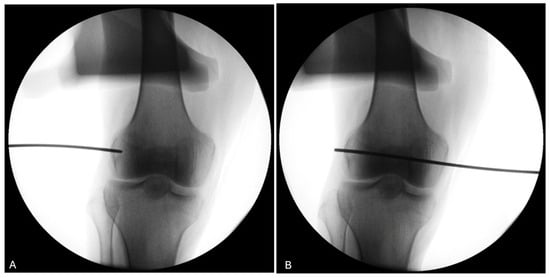

The use of a fluoroscopy device during the procedure (knees 5 to 8) demonstrates its utility in ensuring the proper positioning of the trocar for the four knees of donor #3 and #4 (Figure 10).

Figure 10.

Fluoroscopy of the right knee of donor #4. (A) The use of fluoroscopy on a right knee (donor #4) confirms that the pin entry point (black line) is well-centered visually on the LFE on the antero-posterior view. (B) The pin is advanced medially to exit through the medial condyle.

No formal intra operator reliability assessment was conducted however, guide wire positioning was retrospectively verified. In the first four knees, CT imaging was used retrospectively to verify trocar positioning due to an unexpected failure of the fluoroscopy unit. Once fluoroscopy was operational, it was used intraoperatively for the remaining knees. The use of both imaging modalities ultimately reinforces the applicability of our protocol, as it demonstrates that trocar positioning can be reliably assessed using either CT or fluoroscopy, depending on equipment availability in laboratory settings. All procedures were performed by a fellowship-trained orthopedic surgeon specializing in sports medicine. In one of the CT-evaluated knees, a misalignment greater than 6 mm was observed. This was on the first specimen, and the surgeon indeed noted a slight glide of the tip of the pin at insertion. A more careful insertion technique was then used to avoid the same mistake. However, the light-defined point used for measurements remained stable, and the average relative displacement between 0° and 30° of flexion was therefore unaffected. The use of fluoroscopy gives direct inputs on proper pin placement on the antero-posterior (AP) view and may be a less expensive technique. On the other hand, since the LFE is impossible to locate from the lateral view, it leaves only the AP view to locate the projection of the contour of the LFE. This may lead to undetected anterior or posterior placement of the wire. Both techniques therefore have their limitations. The best scenario would be to insert the wire, use the CT scan to validate the proper position, and then bring the cadaveric knee back to the lab to move on with the measurements. In our setting, this was not practicable.